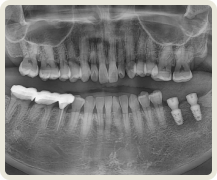

아날로그 치료 잘못된 예

이로운치과의 문제 예방이로운치과의 문제 예방이로운치과의 문제 예방이로운치과의 문제 예방

잘 못 심은 임플란트의 예시입니다.

이로운 치과는 디지털 진료를 통해 정확한 임플란트 식립 위치를 파악하여

아날로그 치료에서 발생할 수 있는 문제를 예방합니다.